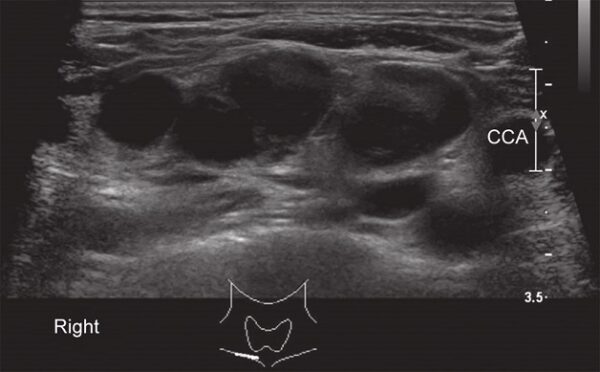

Siêu âm là một phương pháp chẩn đoán hình ảnh không xâm lấn, sử dụng sóng âm cao tần để tạo ra hình ảnh của các cơ quan và mô trong cơ thể. Siêu âm có thể được sử dụng để chẩn đoán u hạch bạch huyết bằng cách đánh giá các đặc điểm của u hạch, bao gồm:

U hạch bạch huyết là một loại ung thư bắt nguồn từ các tế bào bạch huyết trong u hạch. Siêu âm chẩn đoán u hạch bạch huyết là một phương pháp hình ảnh y tế sử dụng sóng siêu âm để tạo ra hình ảnh của u hạch và các cơ quan xung quanh.

Vị trí của u hạch nằm ở phía trên của bụng, phía trước của đùi, và phía dưới của xương sườn. Để chẩn đoán u hạch bạch huyết bằng siêu âm, bác sĩ sẽ sử dụng một máy siêu âm để tạo ra hình ảnh của u hạch và các cơ quan xung quanh. Hình ảnh này sẽ giúp bác sĩ xác định kích thước, hình dạng và vị trí của u hạch, từ đó đưa ra chẩn đoán chính xác và kế hoạch điều trị phù hợp.

Siêu âm có thể đánh giá hình dạng của u hạch, bao gồm đối xứng và đường viền.

Độ hồi âm của u hạch có thể được đánh giá bằng cách sử dụng siêu âm.

Siêu âm có thể đo kích thước của u hạch.

Siêu âm có thể đánh giá tính ác tính của u hạch bằng cách đánh giá các đặc điểm của nó, bao gồm kích thước, hình dạng và độ hồi âm.